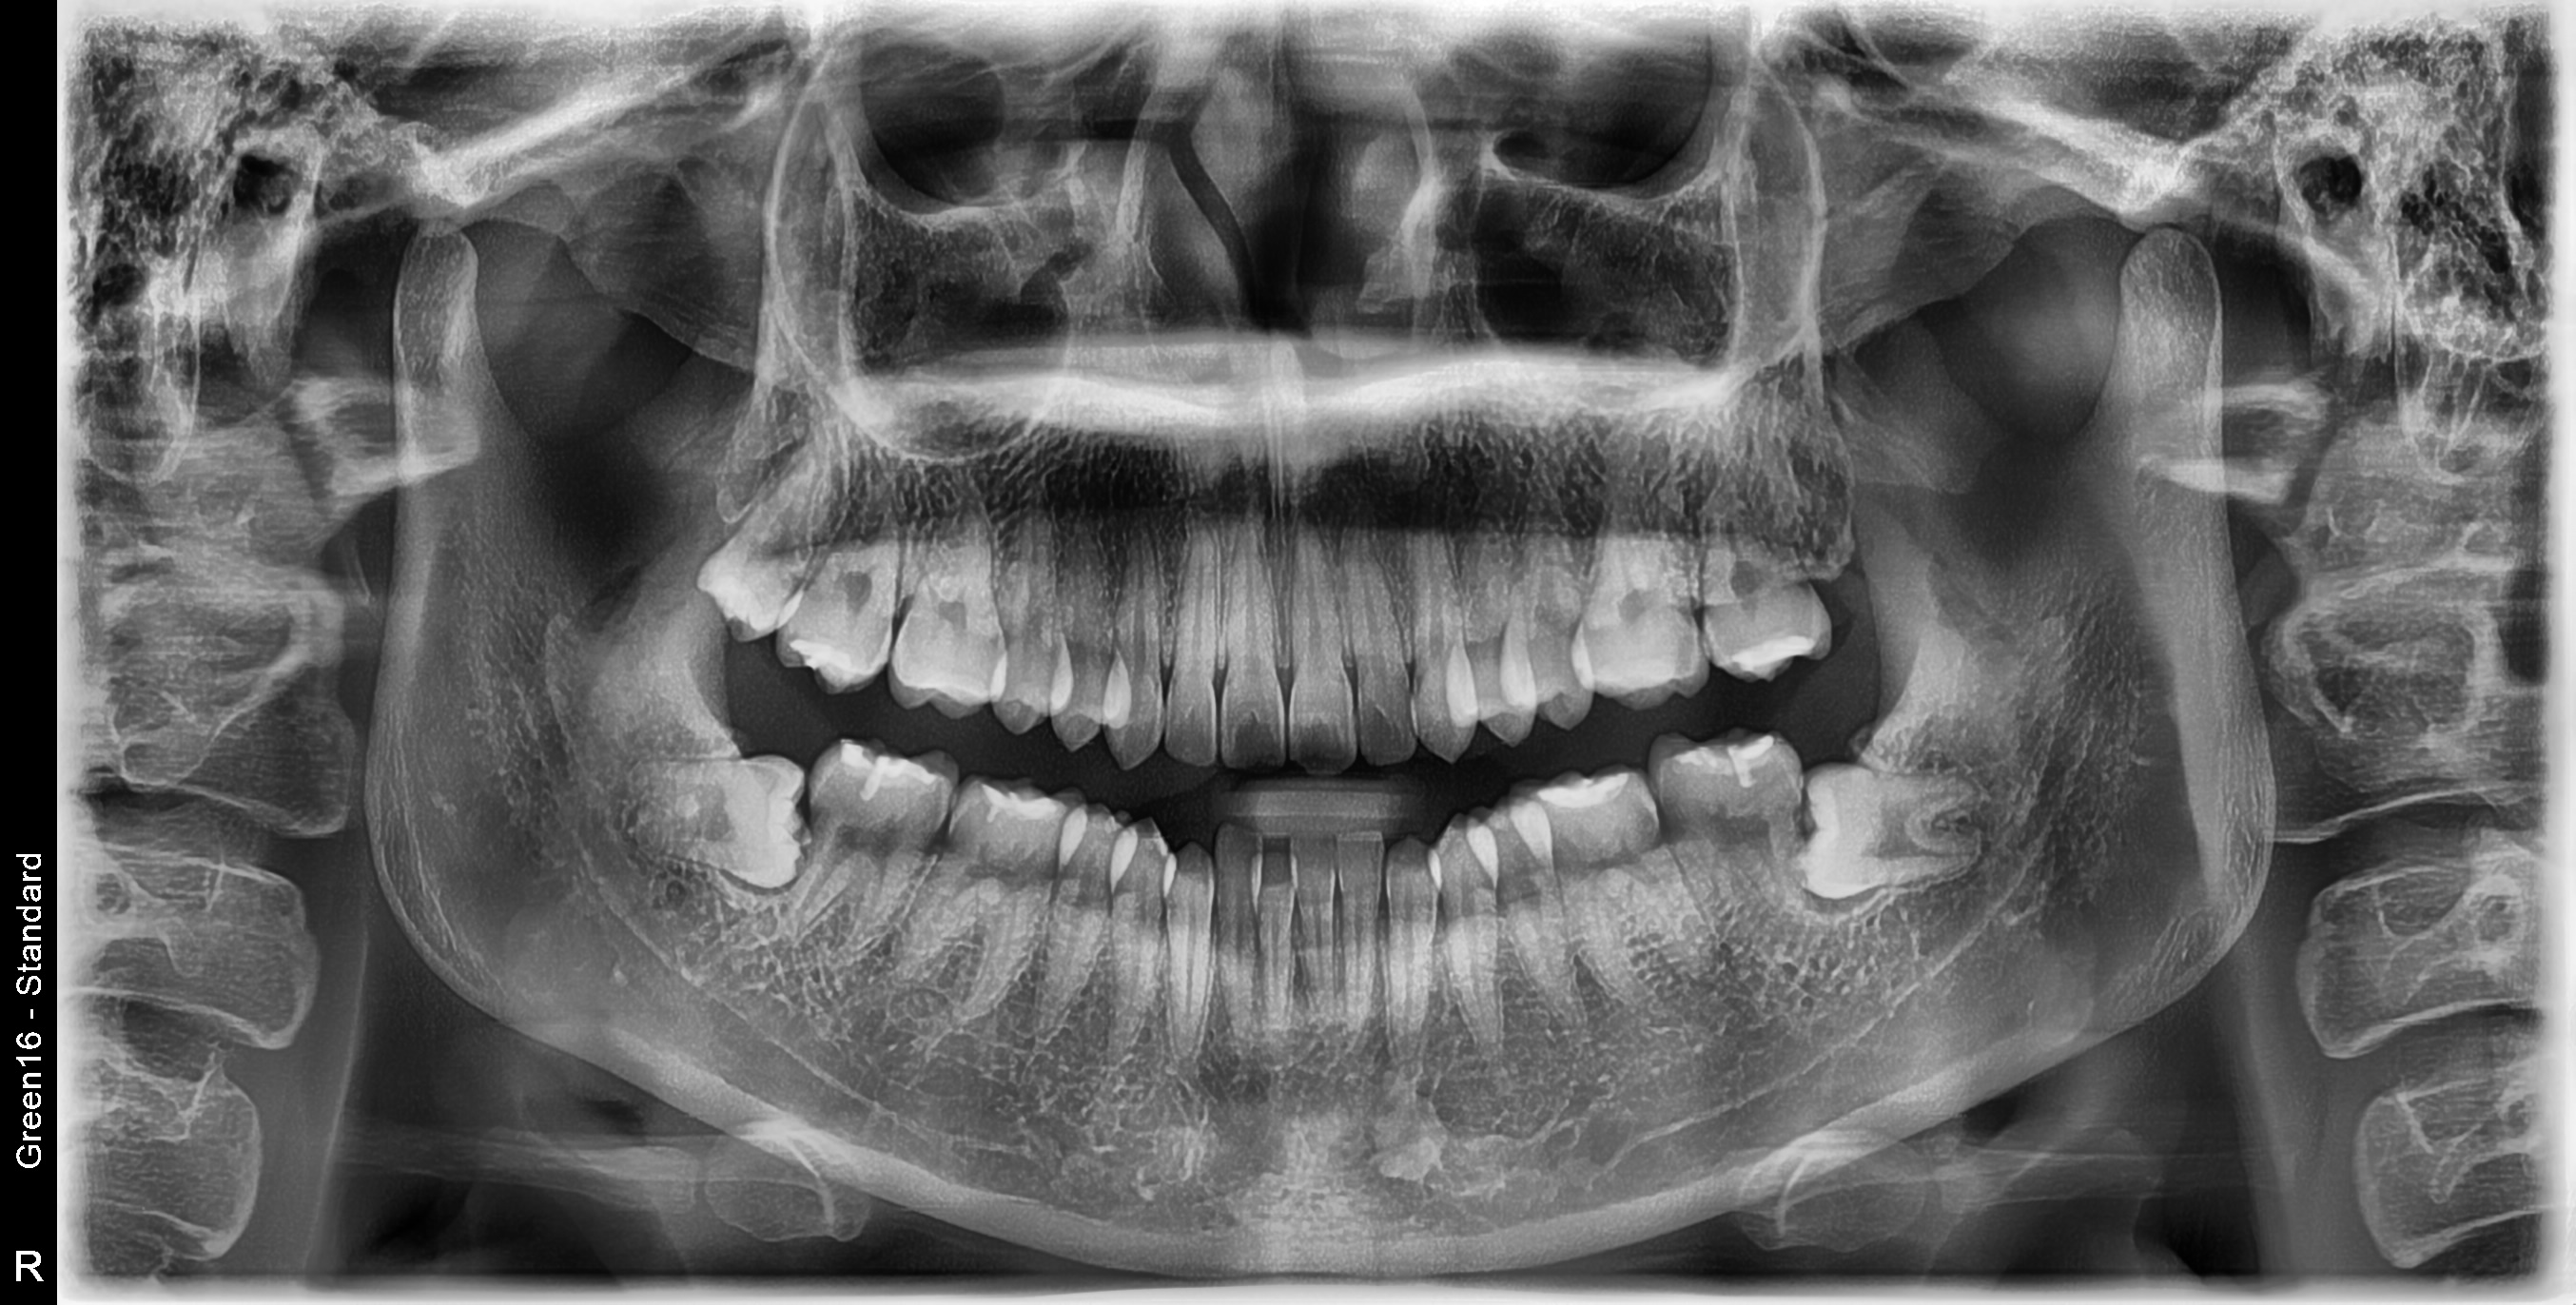

수술 전

수술 후

하악 임플란트 식립사례

전후사진